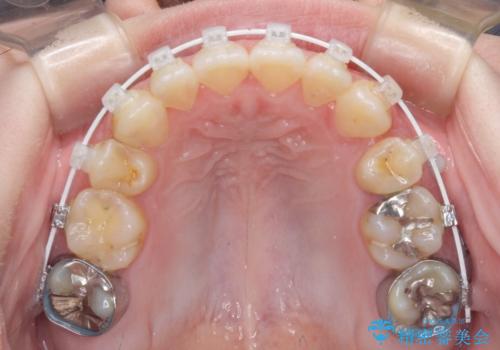

- 矯正装置

- 審美装置

- 左上の八重歯と前歯のデコボコを気にして来院された患者様です。

下顎が左側にズレており、下顎前歯は1歯欠損していたため、左上小臼歯1本を抜歯し、ワイヤー装置にて矯正治療を行うこととしました。

骨格のズレと歯の欠損があったため、仕上がりの調整に時間がかかると思いましたが、舌突出癖の改善や顎間ゴムの装着をしっかりと行ってくださったので、速やかに治療を終えることができました。